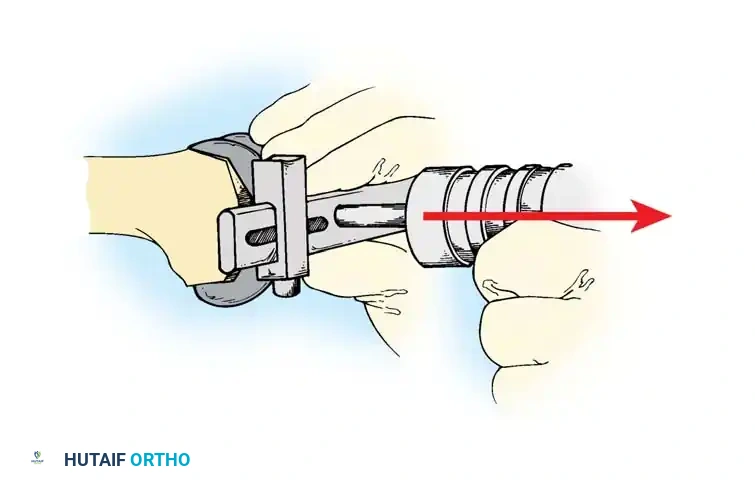

Removing the Femoral Component

The femoral component is addressed by systematically disrupting the cement mantle or ingrowth surface at the anterior flange, distal condyles, and posterior chamfers using thin, flexible osteotomes.

Fig. 6-82 Systematic disruption of the femoral bone-cement interface.

Once the interfaces are free, a slap hammer or extraction device is applied to the intercondylar notch or modular lugs to gently back the implant off the bone in the axis of its original insertion.

Fig. 6-83 Application of a slap hammer for controlled axial extraction of the femoral component.